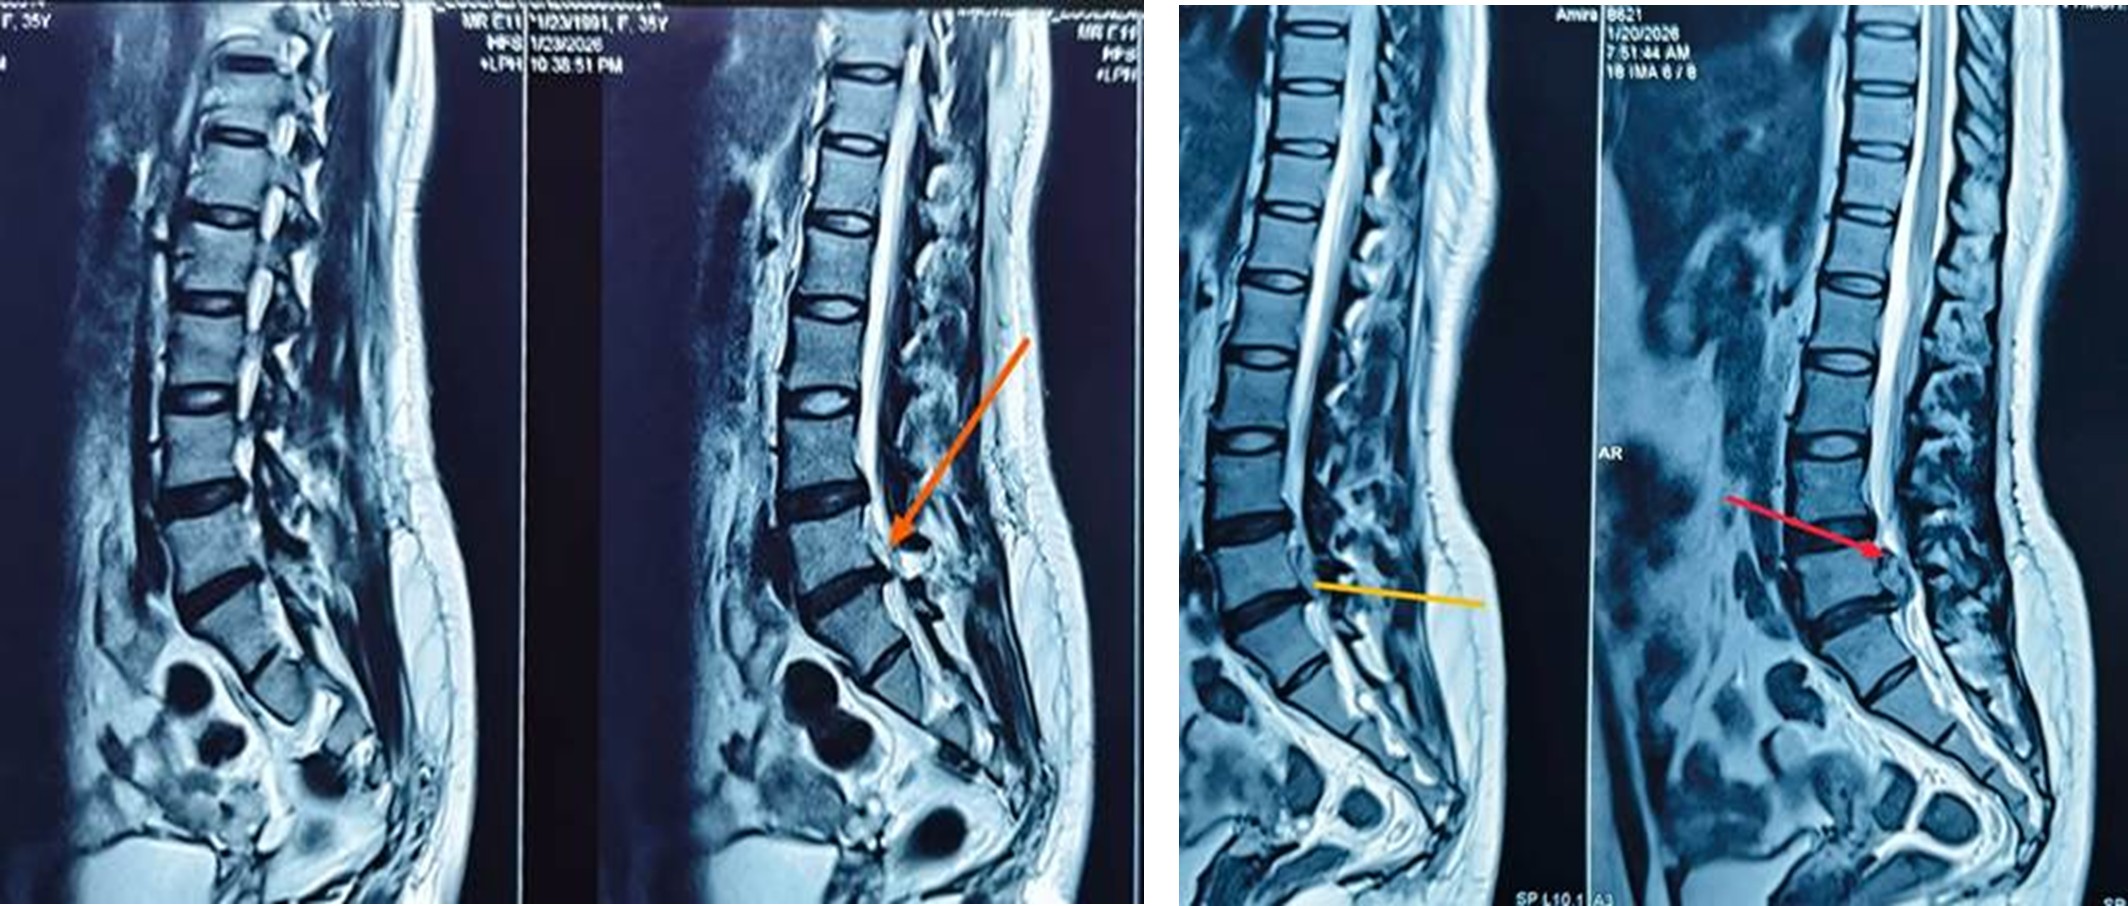

Lumbar disc herniation is a common cause of low back pain and sciatica, often affecting the working-age population. While conservative management remains the first-line treatment, surgery is indicated in patients with persistent pain, neurological deficit, or failed non-operative therapy. Endoscopic spine discectomy has emerged as an effective alternative to conventional discectomy, offering comparable clinical outcomes with reduced morbidity.

Intervertebral disc herniation is one of the most common causes of back pain and radiculopathy, significantly affecting patient mobility and quality of life. Traditionally, open discectomy and microdiscectomy are considered standard surgical treatments for patients who do not respond to conservative management. However, these procedures involve muscle dissection and bone removal, which may lead to postoperative pain, longer recovery time, and potential spinal instability.

Advancements in minimally invasive spine surgery have led to the development of endoscopic spine discectomy. This technique uses a small skin incision and muscle-splitting approach, allowing direct visualization of the herniated disc through an endoscope. The procedure minimizes tissue trauma and promotes faster rehabilitation while maintaining spinal stability. Due to these benefits, endoscopic discectomy is increasingly being adopted worldwide as a safe and effective treatment option for selected lumbar and cervical disc herniations.